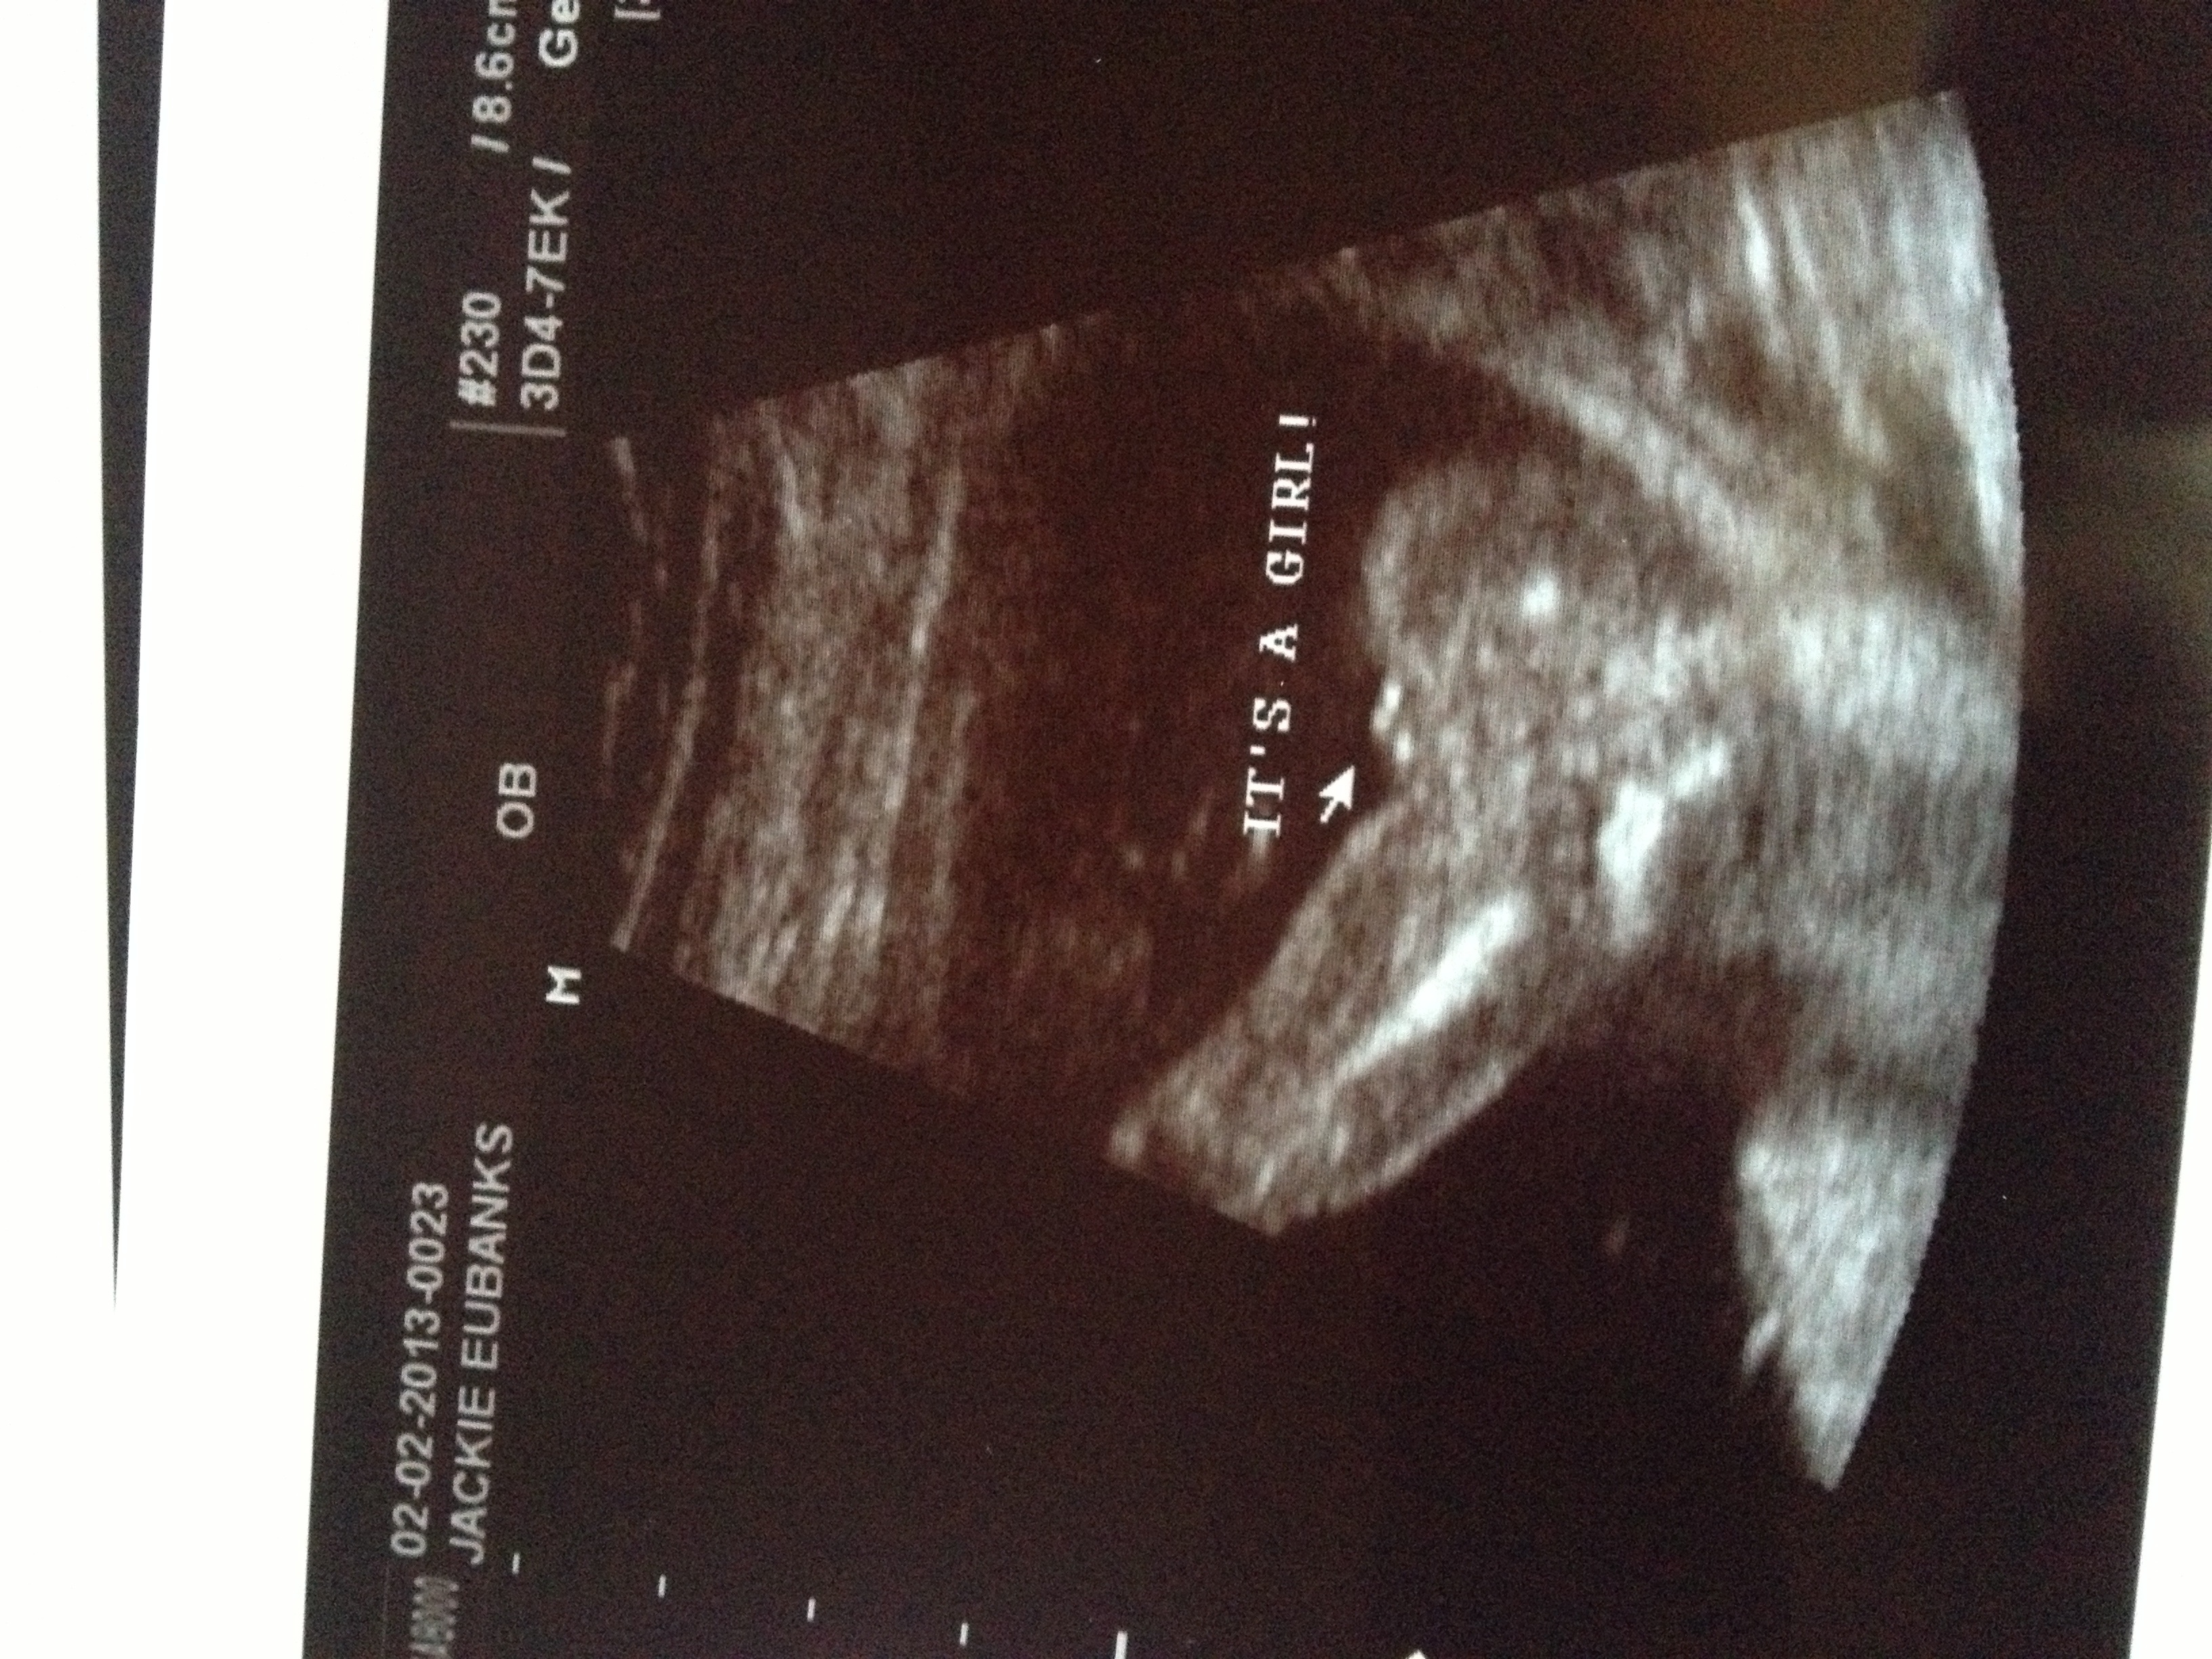

Attachment 8593Attachment 8594UPDATE! It's a girl! Thanks for all the guesses! Y'all made waiting much easier!

Congrats!!!! I'm also due in July with a girl! :)

YAY! congrats on your daughter :) x

Great pic of girl parts--congrats!